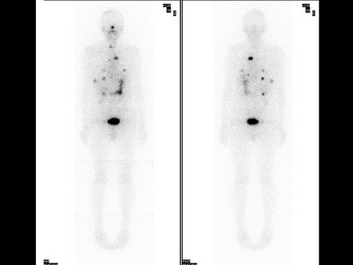

15、多项选择题

63岁男性,甲状腺滤泡状癌术后3年,行I全身显像及SPECT/CT图像融合如图,正确的诊断是()